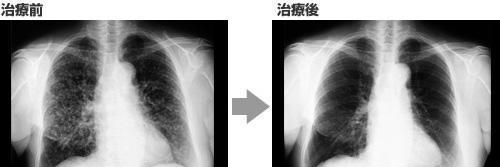

案例1:肺癌

双侧肺发生大大小小的病变的肺腺癌

抗癌剂和高度活性化NK细胞疗法*管双**齐下,结节基本消失!

高度活性化NK细胞疗法完美地完成他的使命!

75岁 女性

在2015年7月被确诊为【肺癌(肺腺癌)】。

能看出双侧肺部存在大量大大小小的结节,不适用于手术和放疗。

只适用于抗癌剂治疗。

因13年前有过乳腺癌病史,加上这次只用抗癌剂的话,患者比较担心其治疗效果,因此在2015年8月开始并用抗癌剂治疗和高度活性化NK细胞疗法。

每两周进行一次高度活性化NK细胞治疗。

首次进行抗癌剂静脉滴注时,由于副作用大,患者身体上、精神上都很痛苦。

第二次开始,以口服抗癌药易瑞沙代替静脉滴注,没有副作用,安稳地度过日常生活。

治疗开始前的肿瘤标志物是:

细胞角蛋白:5.6(正常值2.0ng/ml以下)、NSE·CA15-3为正常值以内。

高度活性化NK细胞疗法5次治疗后的肿瘤标志物是:

细胞角蛋白:1.0,比正常值低,NSE·CA15-3都在正常值以内,比以前更低了。

高度活性化NK细胞疗法11次治疗后的肿瘤标志物是:

细胞角蛋白:0.5,NSE·CA15-3全部都在正常值以内,甚至更低了。

影像检查情况:

进行3次高度活性化NK细胞治疗后,主要肿瘤有缩小趋势,多发结节也逐渐消失。

进行12次高度活性化NK细胞治疗后,主要肿瘤消失,双侧多发结节也基本消失。

此疗法没有像抗癌剂那样的副作用,能够正常生活,这对于患者来说,无疑是最好的治疗。

该患者在2016年2月暂停使用高度活性化NK细胞疗法,继续使用抗癌剂治疗。